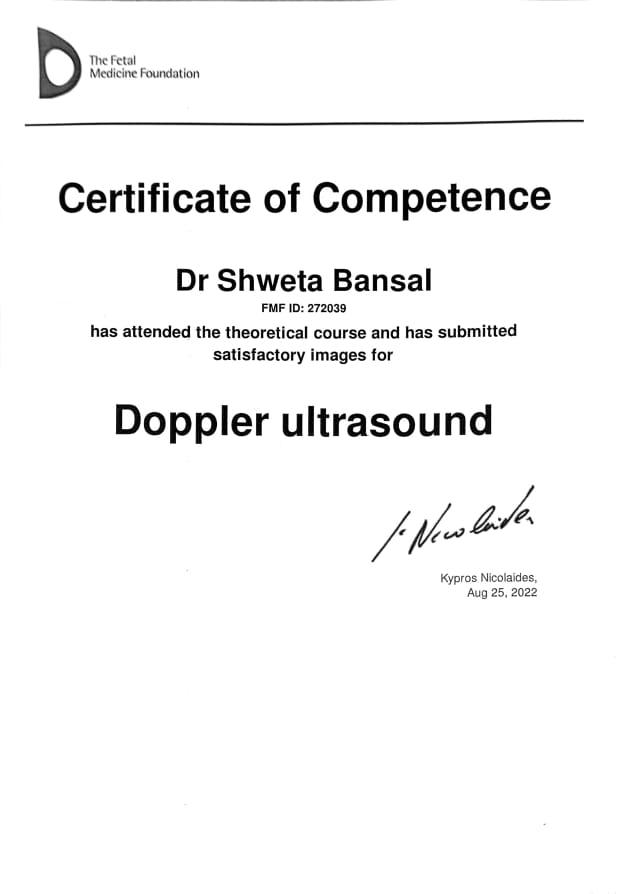

Dr. Shweta Diagnostic & Child Care Centre

Expert Care in Fetal Medicine, Pediatrics & Diagnostics

Your trusted destination for compassionate and advanced healthcare — from pregnancy to childhood and beyond. We specialize in fetal medicine, pediatric care, and precision diagnostics, all under one roof for your family’s complete wellness.